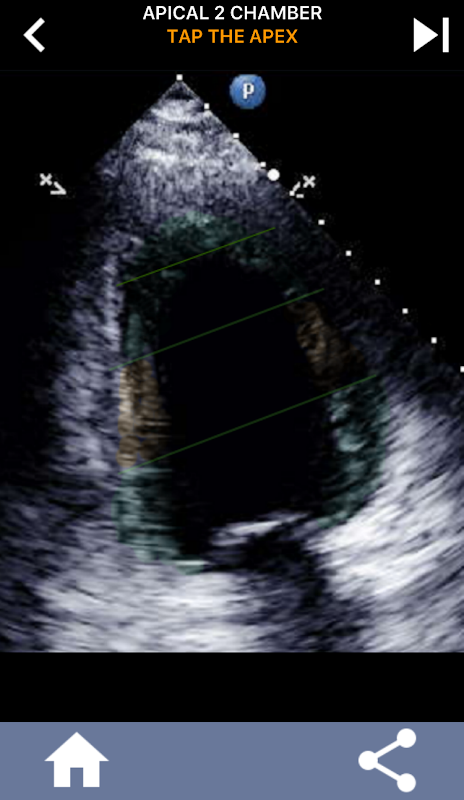

This app contains all the echo views showing the AHA segmented myocardium and will quiz you to tap the correct segment. I personally find that repetitive quizzing works best for me when I need to quickly learn/memorize subject. If you are an ultrasound student studying echo/TTE I think this would be an excellent complement to your studies.